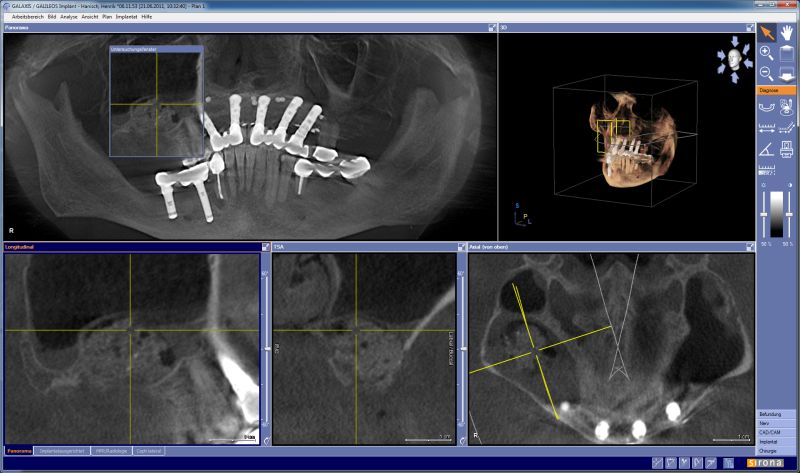

GBR with maxresorb® and collprotect® membrane - Dr. G. Bayer

DVT image showing the reduced amount of bone available in the area of the mental foramen